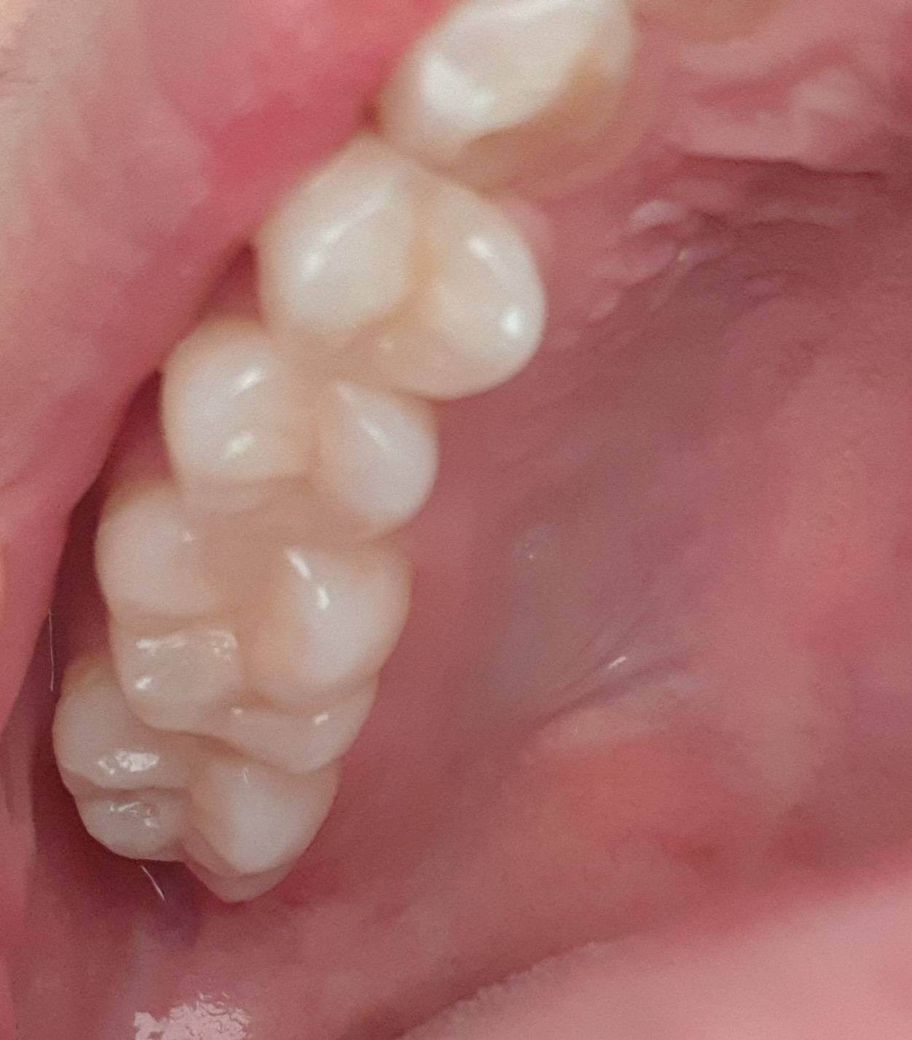

• 2번 째 사진

왼쪽 윗 어금니에 가끔식 통증이 와요.

처음 닿을때 살짝 시린느낌?신경이 아픈느낌? 이고 그다음부터는 닿아도 상관없는데 왜이러죠

치과 가서 검사해도 별 이상은 없다고 시간 지나면 괜찮아 진다고 스케일링만 받고왔네요.